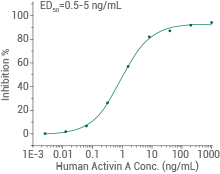

Human/Mouse/Rat/Cynomolgus/Rhesus activin A protein

Measured by its ability to inhibit the proliferation of MPC-11 cells. The specific activity is >1000 U/mg. Image Credit: Sino Biological Inc.